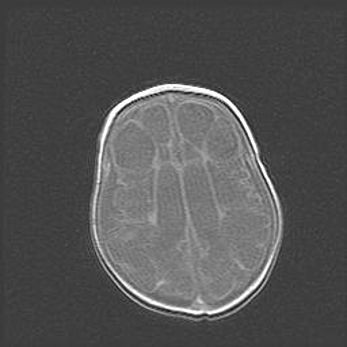

Множественные кисты обоих полушарий головного мозга, наибольшая из них в правой затылочной области. Ассиметричная атрофическая гидроцефалия.

Возраст: 7 месяцев

Вес: 5660 г

Пол: мужской

Окружность головы: 41,5 см

Срок гестации: 28-29 недель

Кисты головного мозга развиваются в результате многоочаговых некрозов вещества мозга и возникают вследствие перенесенной перинатальной инфекции, менингитов, энцефалитов, асфиксии, родовой травмы, расстройств мозгового кровообращения различного генеза. Образованию кист в веществе головного мозга плодов и новорожденных способствуют такие факторы, как высокое содержание в нем воды, недостаточная (или отсутствие) миелинизация и слабая астроглиальная реакция на повреждение.

Кисты могут сочетаться с гидроцефалией и другими поражениями головного мозга.